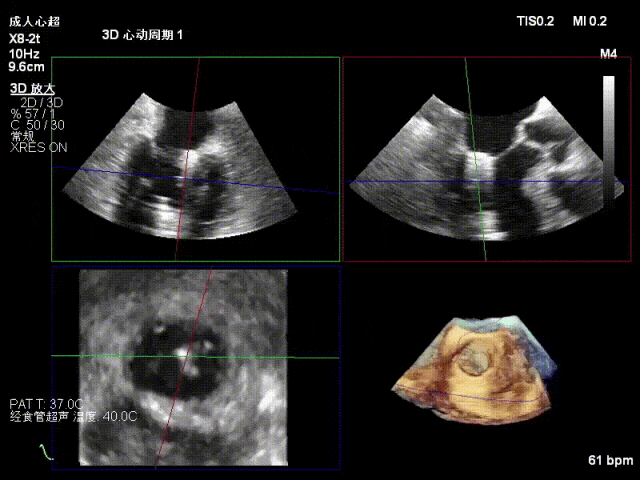

术中超声要点

功能性MR,P3脱垂,新分型:BAA型

反流主要集中于3区,MR中度,VC:2×4mm

A2:24mm,P2:16mm,AP:38mm,MVA约4.6cm²